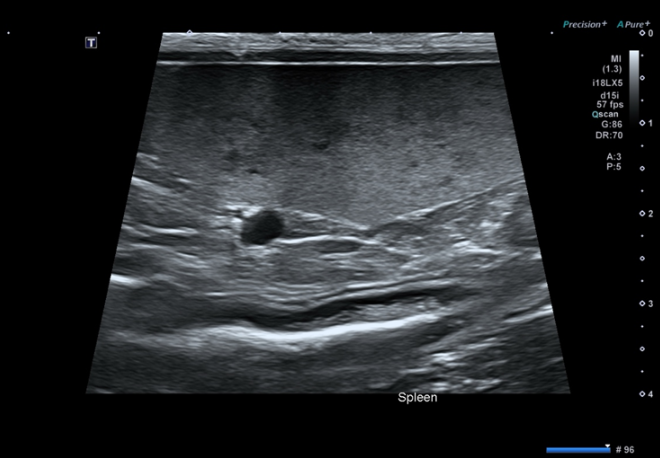

그림 2. 비장의 벌집 징후(honeycomb sign)

비장에서 벌집 징후(honeycomb sign) 관찰

→ 종양에서 특징적으로 보일 수 있는 소견